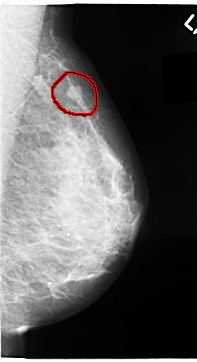

C_0065_1.RIGHT_MLO

LEFT_MLO LINES 4704 PIXELS_PER_LINE 2552 BITS_PER_PIXEL 12 RESOLUTION 50 OVERLAY

FILE: C_0065_1.LEFT_MLO.OVERLAY

TOTAL_ABNORMALITIES 1

ABNORMALITY 1

LESION_TYPE MASS SHAPE LOBULATED MARGINS MICROLOBULATED

ASSESSMENT 4

SUBTLETY 5

PATHOLOGY MALIGNANT

TOTAL_OUTLINES 1

BOUNDARY